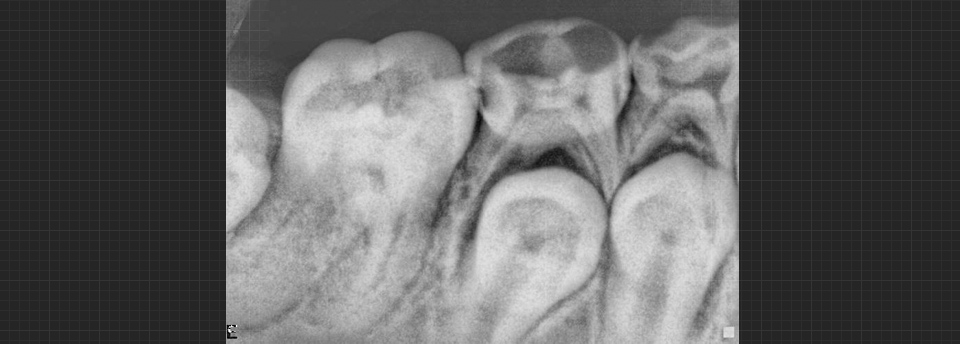

We enjoy working with children of all ages and feel it is very important to begin dental health early. Our patients are 3 years and up. Many dental problems can be intercepted and treated easily if diagnosed early. Our office offers sealants, fillings, crowns, extractions on “baby” teeth and adult teeth. We offer screening for future orthodontic treatment and have a wonderful team of specialists to help make difficult cases easy. Click here to find out more.